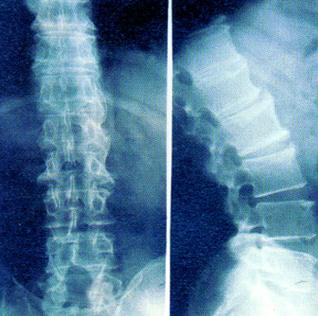

强直性脊柱炎

QZ16030094 姓名:陈先生 性别:男 年龄:32岁

- 病情

AS ①晚期 ②重度 病史:5年+

- 治疗

治疗后骶髂关节疼痛消失,腰椎前屈、背伸侧弯活动自如,膝关节无压痛感,复查血沉、C反应蛋白、等各项检查均已达到临床康复的标准。